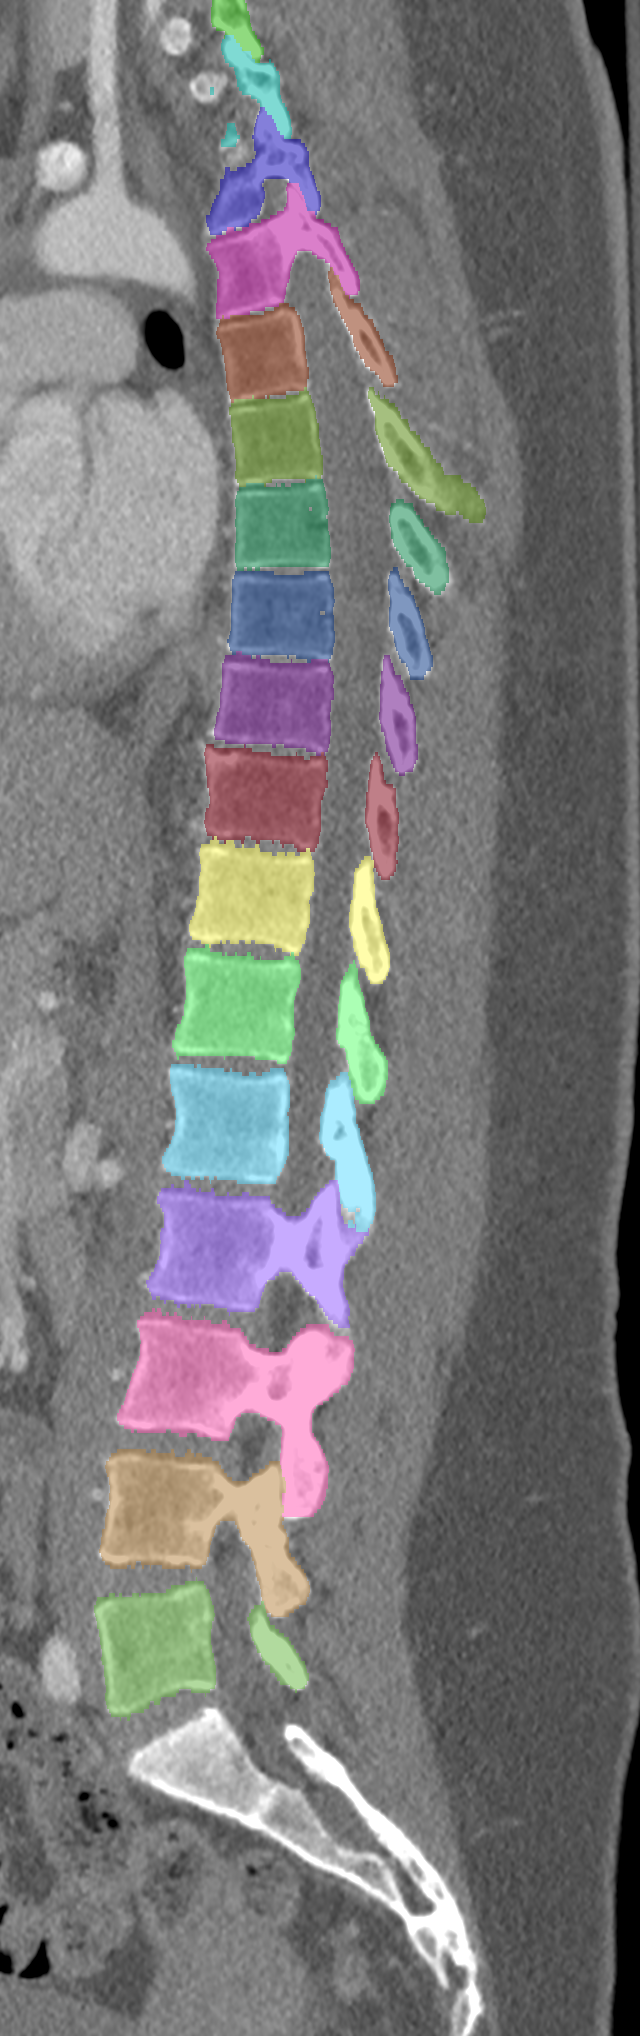

Normalized CT images and reference segmentations of thoracic and lumbar vertebrae from the CSI 2014 workshop

Description

This is the dataset of the vertebra segmentation challenge of the CSI 2014 workshop that was held in conjunction with MICCAI 2014.

- Vertebrae have been anatomically labeled (8 = T1, 9 = T2, ..., 24 = L5)

- Because not always all visible vertebrae were segmented in the original data, only segmentations of the thoracic and lumbar vertebrae have been retained